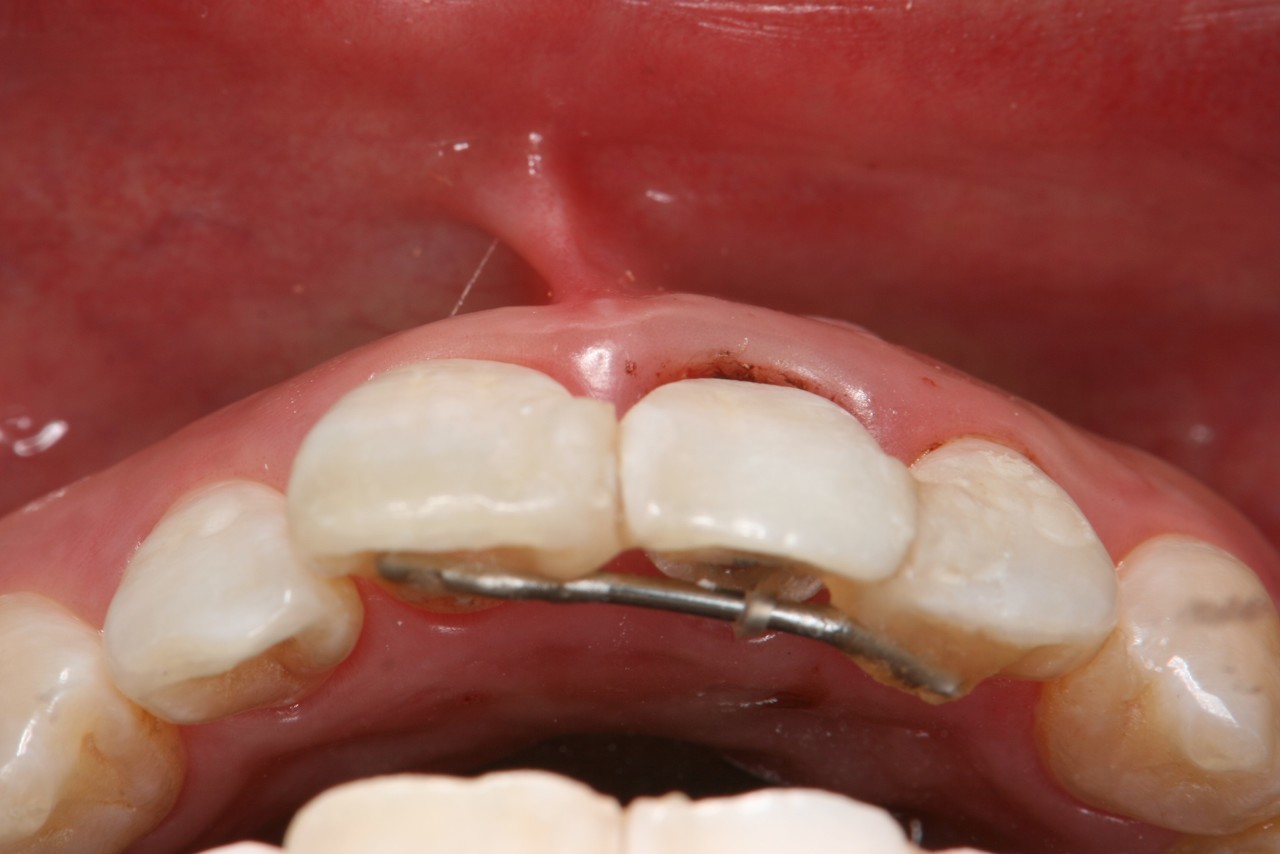

矯正的挺出(エクストルージョン)の症例

• 30代女性の患者さま

• 過去に何度も歯の根の治療をしていて、とうとう歯の根が折れてしまったとのことで来院。

• 初診時の状態は、歯が折れているため隣の歯と接着された状態であった。他院にて歯を抜くことと、インプラントをすすめられたが、他の方法がないかと当院にご相談。折れた歯の断面の位置によっては、歯の根を引っ張り上げることにより歯を保存できる可能性を説明して治療を開始。

• 治療期間 約6か月

1.折れてしまった歯

2.歯の根の折れた部分は歯ぐきの下にあります

3.矯正的挺出中(引っ張り上げる)の写真

4.治療終了後

きれいに歯が復活しました